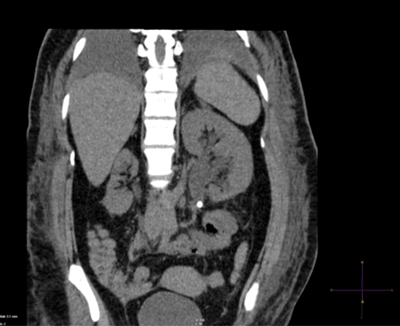

Case 4

-

Plain CT KUB, coronal reconstruction demonstrating left PUJ stone with associated hydronephrosis.

4.5mSv

Quick scan (20-30 seconds), easy to interpret, no IV contrast needed, can establish differential diagnosis.

Sensitivity >95%, specificity >96%.